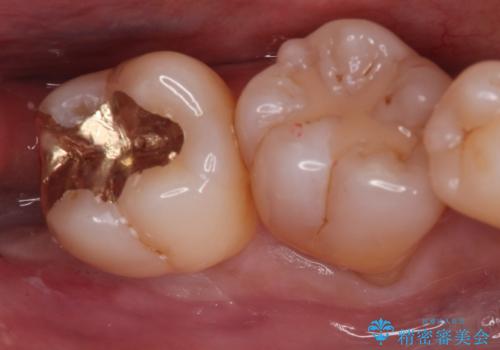

メタルインレーからセラミックインレーへ

セラミックインレーに治療を行っております。

e-max プレスインレーにて修復治療を行っているため適合性及び審美性の高い治療を行うことができます